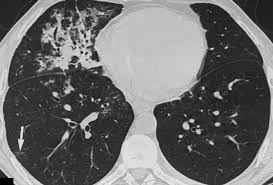

Pneumonia is a significant health concern worldwide, affecting millions every year. It is an infection that inflames the air sacs in one or both lungs, which may fill with fluid or pus, causing cough with phlegm or pus, fever, chills, and difficulty breathing. The importance of understanding pneumonia lies in its potential severity and its role as a leading cause of death among children and the elderly. Global health authorities emphasise awareness of symptoms and appropriate treatment options, especially in light of the COVID-19 pandemic, which has heightened the focus on respiratory illnesses.

Pneumonia can be caused by various infectious agents, including bacteria, viruses, and fungi. The most common type is bacterial pneumonia, often caused by *Streptococcus pneumoniae*. Viral pneumonia, frequently exacerbated by common viral infections like influenza, has also been a significant focus recently due to its association with COVID-19. Fungal pneumonia, while less common, can occur in individuals with weakened immune systems.

Symptoms of pneumonia can vary from mild to severe and typically include cough, chest pain, fever, and shortness of breath. While some may recover quickly, others, particularly those with underlying health conditions, may experience complications that require hospitalisation. Preventative measures, such as vaccinations against pneumonia-causing pathogens, are critical. The pneumococcal vaccine, in particular, is recommended for certain high-risk groups, including the elderly and those with chronic illnesses.